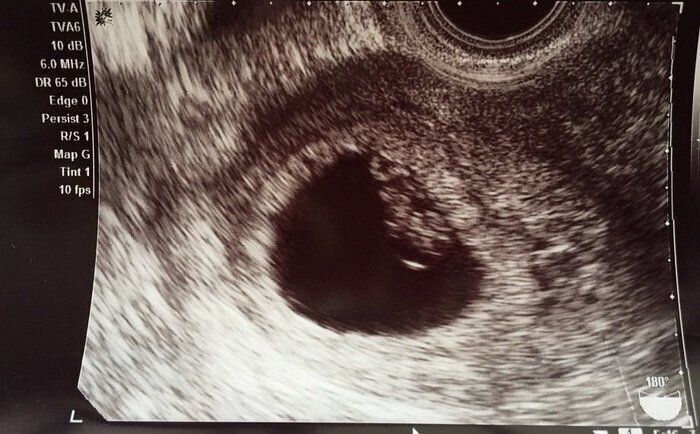

ママにエールさんの妊娠6週目のエコー写真

薄茶色のおりもの(出血)があり、気になって産院へ電話。「とりあえず、診察へ」と言われて受診しましたが、妊娠初期によくある程度の出血だから大丈夫とのこと。出血止めの薬だけ処方されました。ちょうどこの時、エコーで白い小さな粒を確認。「これが赤ちゃんに成長していきます」と先生に聞いて、愛しさでエコー写真をしばらく眺めていました。夫に見せたら、「ちっこい」と笑っていました。